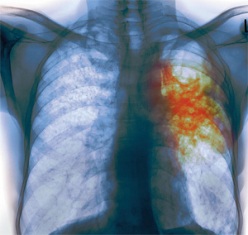

Դիսպանսերն ունի առանձին բաժին, որտեղ տարբեր հոգեբուժարաններից տուբերկուլյոզով հոգեկան հիվանդներ են բուժում անցնում:

«Առավոտի» կողմից ավելացնենք, որ տուբերկուլյոզը ծանր վարակիչ հիվանդություն է, որն անցնում է օդակաթիլային եղանակով: Այսինքն` անկախ նրանից, հոգեկան հիվանդություն ունե՞ր, թե՞ ոչ, հիվանդի` դրսում, առանց բժիշկների հսկողության գտնվելը, վտանգավոր է շրջապատի համար: